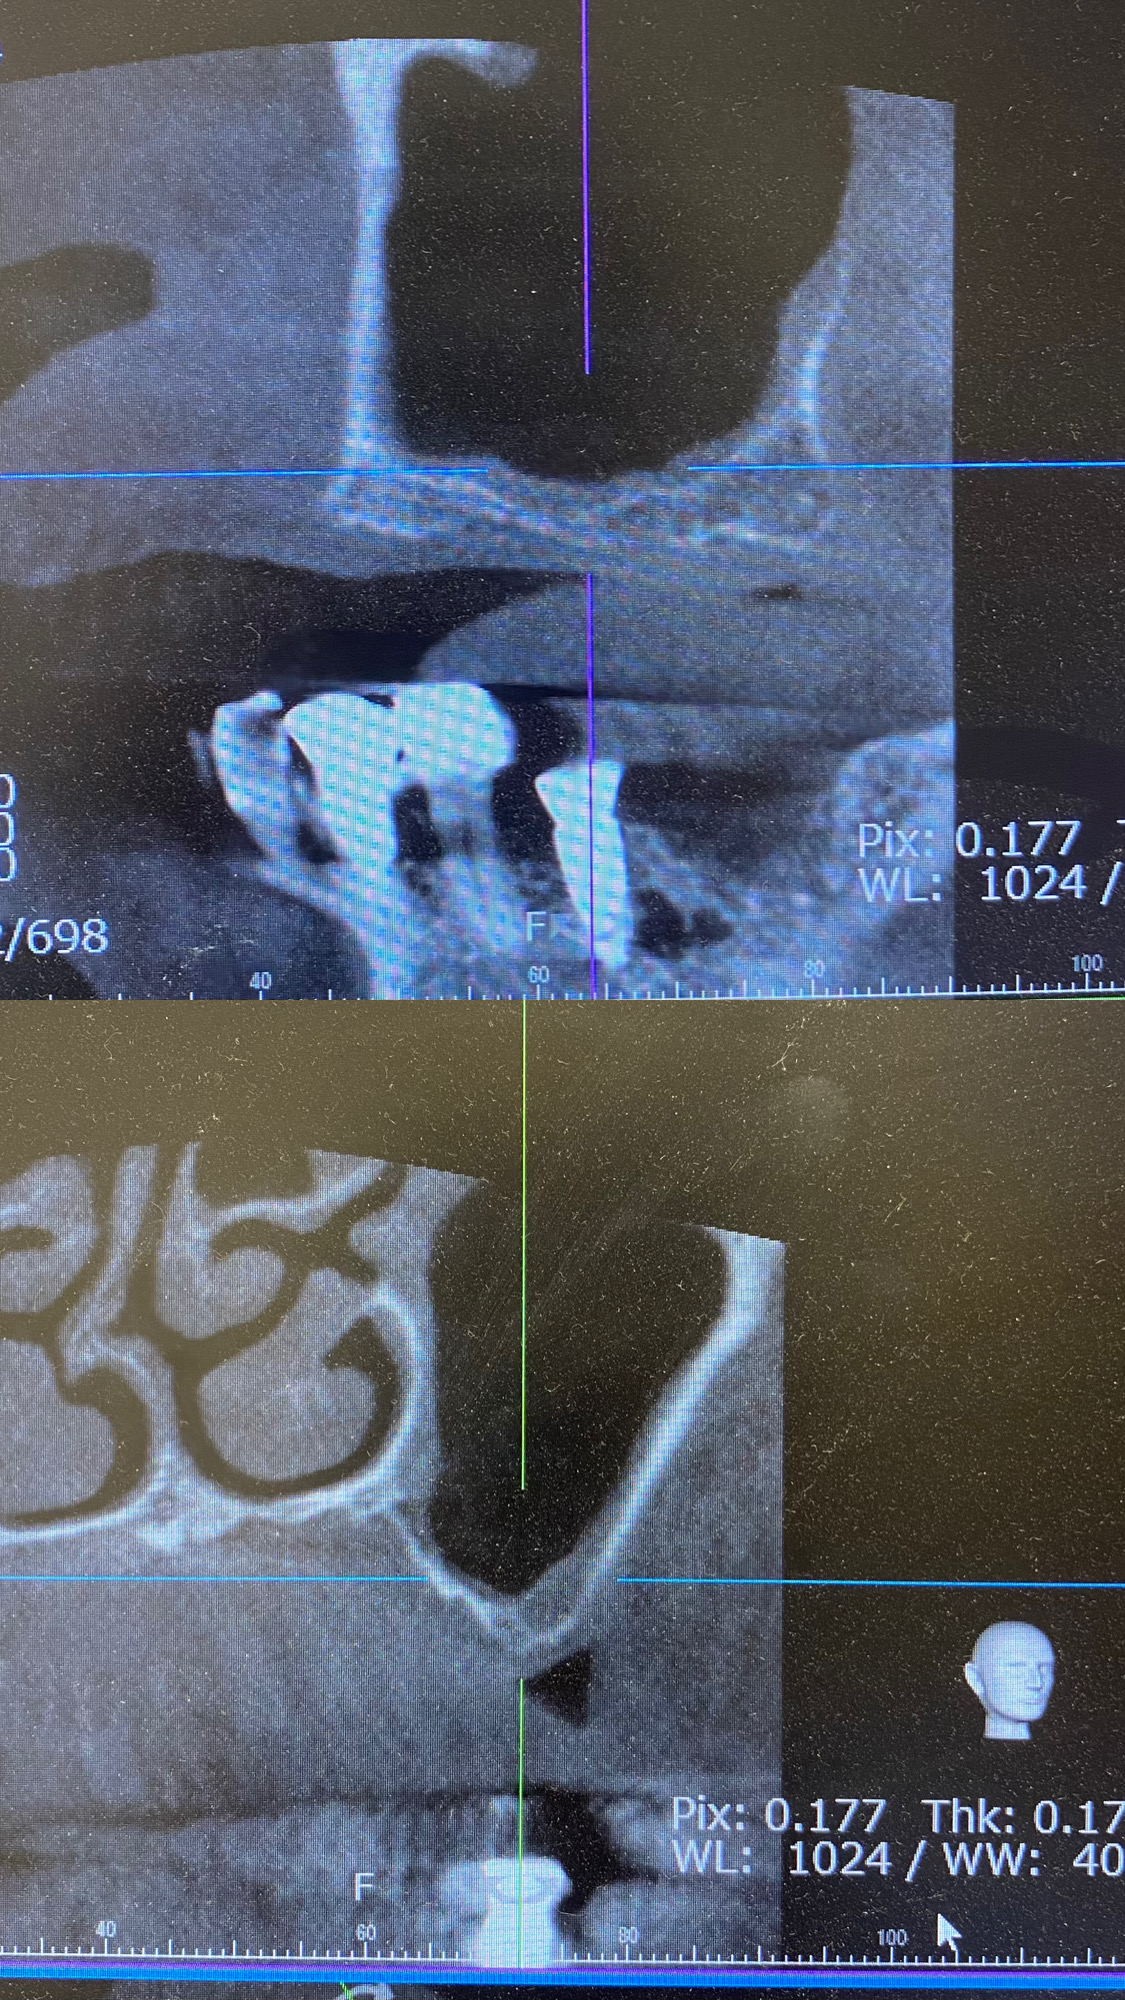

1枚目の写真 GBR前後

2枚目の写真 サイナスリフト後

写真は全て当院で行なった症例です。

①サイナスリフト

上顎奥歯の骨が大幅に不足している場合、上顎洞に骨を増やす手術。

インプラントを同時に埋入できない場合もあります。

③GBR

上顎、下顎共に垂直、水平的に骨がない場合チタンメッシュ、またはコラーゲン膜を用いて骨を増やす手術。

広範囲で行う場合はインプラントを同時に埋入できない場合もあります。